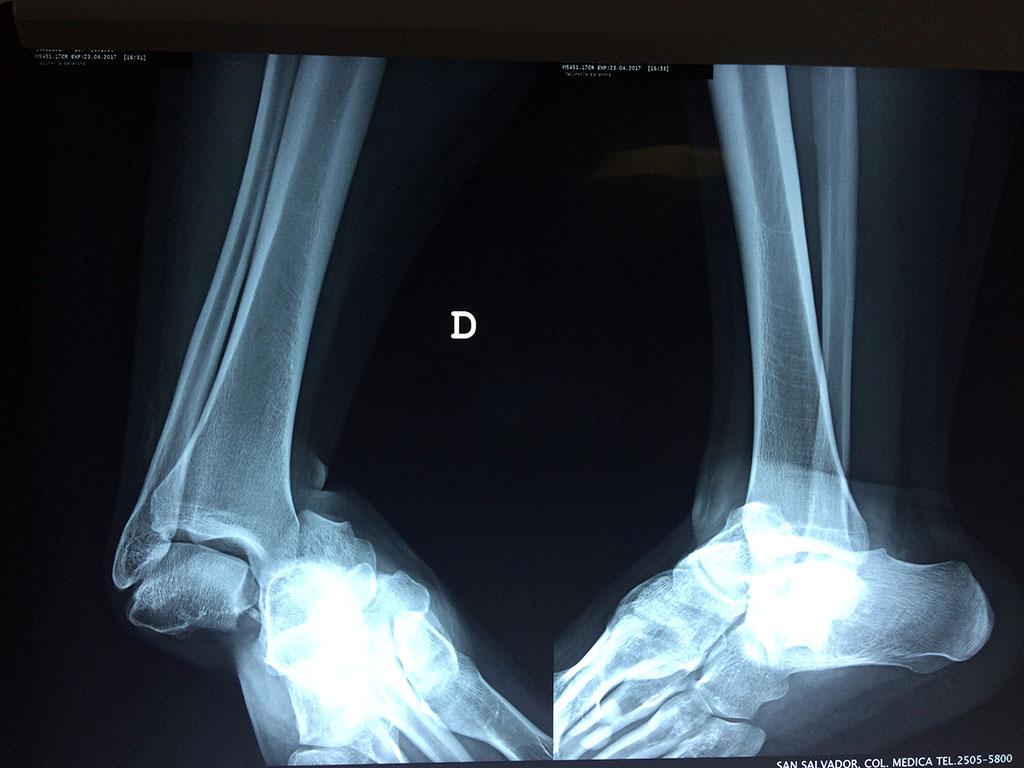

Cirugías de Tobillos

Una fractura de tobillo es la rotura de uno o más de los huesos del tobillo. Estas fracturas pueden ser:

Algunas fracturas de tobillo pueden requerir cirugía si:

- Los extremos de los huesos están desalineados entre sí (desplazados).

- La fractura se extiende hasta la articulación del tobillo (fractura intra-articular).

Cuando se necesita cirugía, es probable que esta implique el uso de clavijas de metal, tornillos o placas para sostener los huesos en su lugar mientras la fractura se consolida. Los elementos de soporte pueden ser temporales o permanentes.